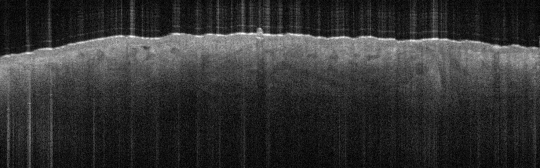

VA15: Right Dorsal Hand, Adjacent, Normal